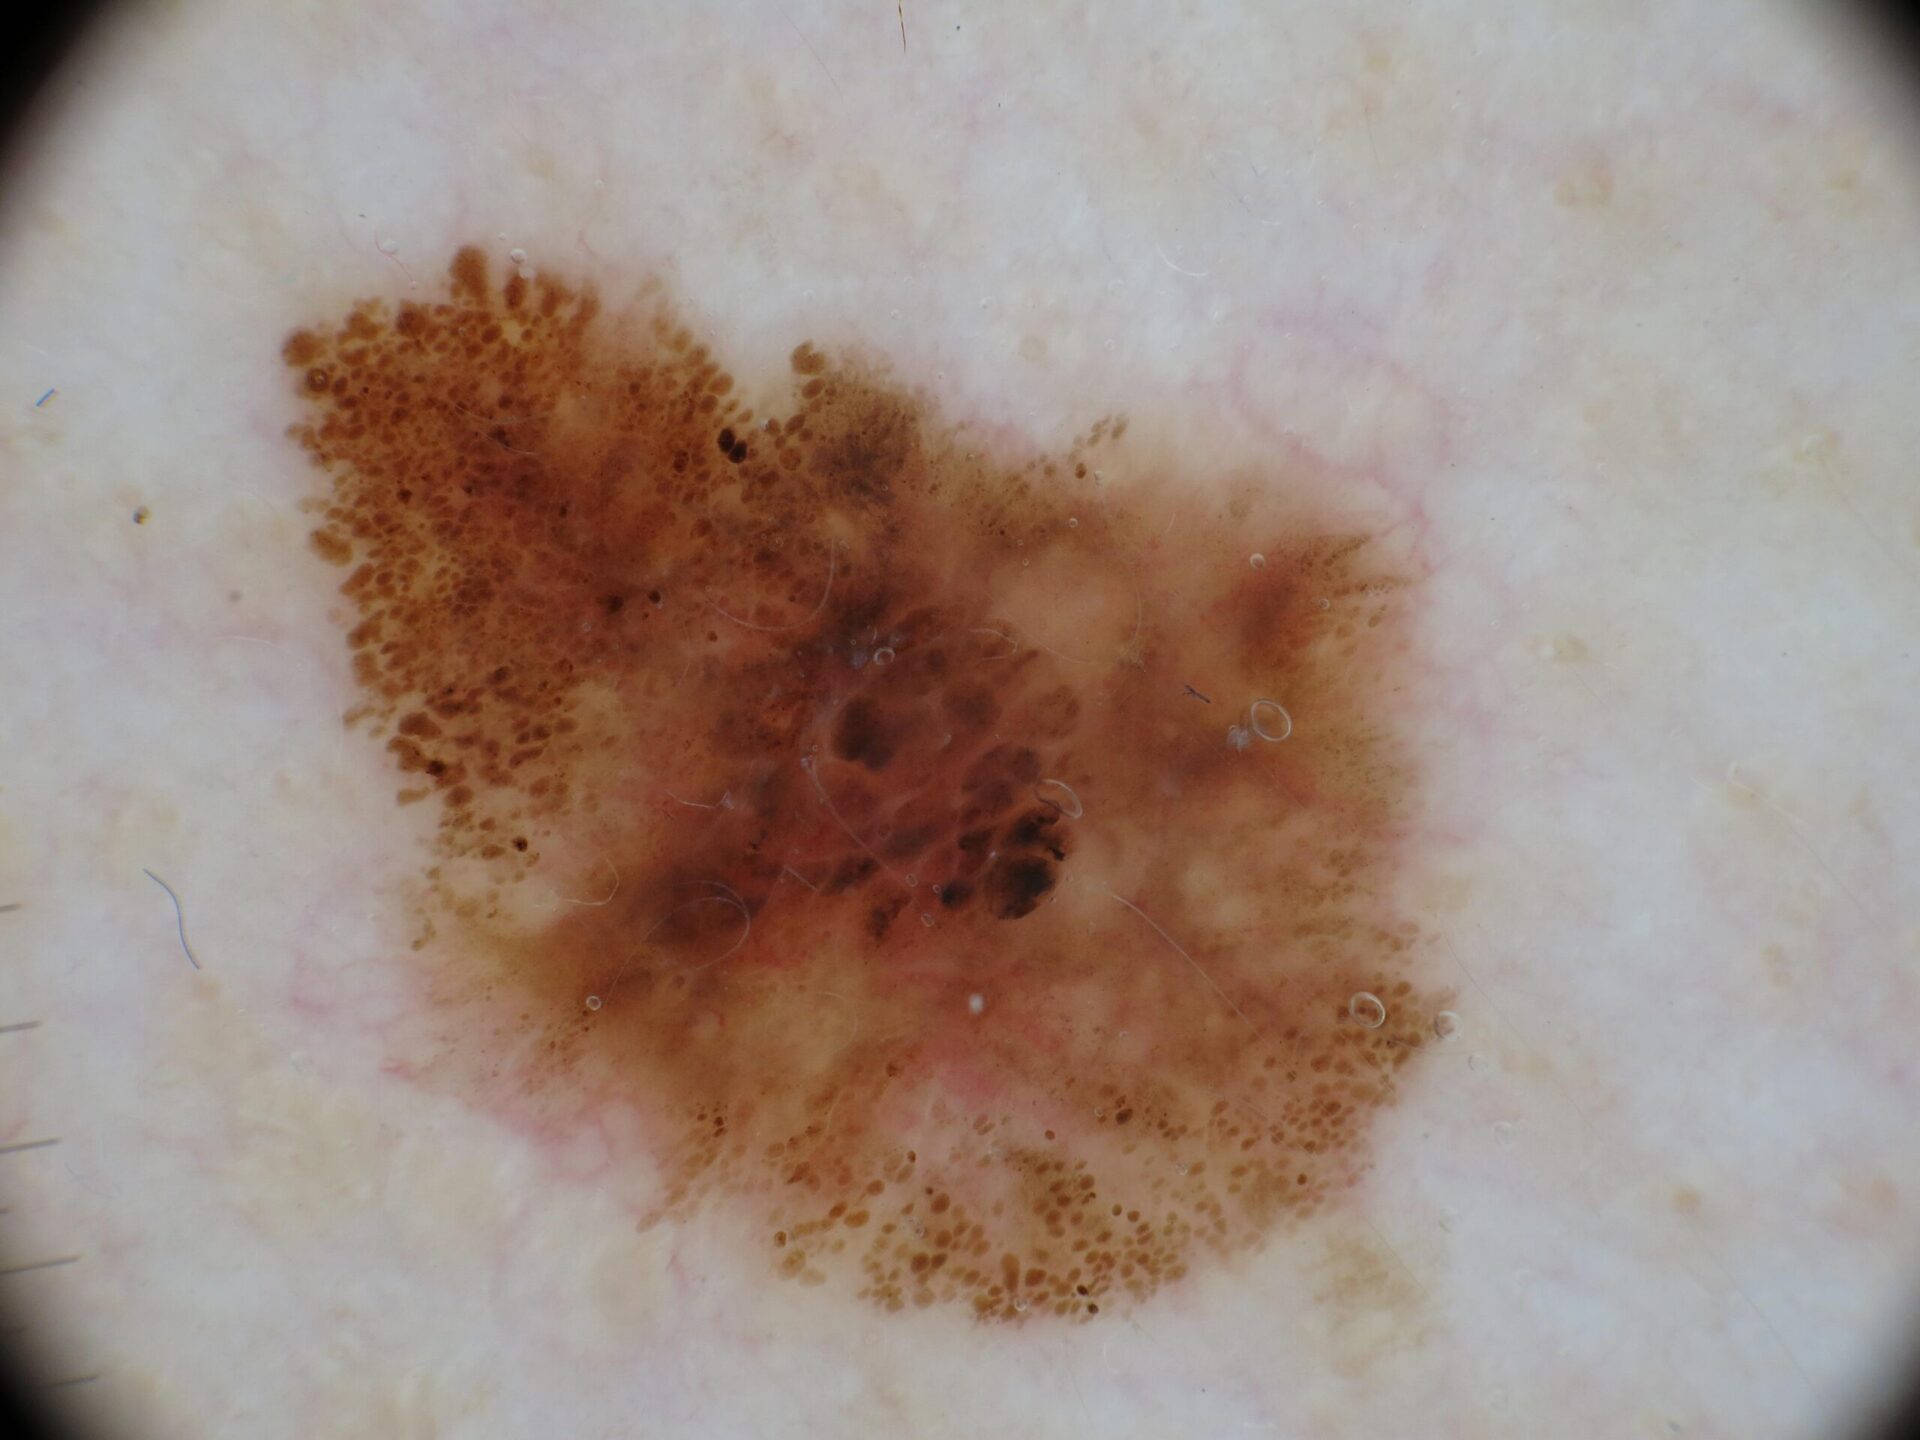

Melanoma Photos

Nodular melanoma on the leg of a Native American woman.

Photo: International Skin Imaging Collaboration

Amelanotic melanomas may be pinkish-looking, reddish, purple, normal skin color or essentially clear and colorless.

Melanoma Case Study

Not a “Boil” but an Advanced Melanoma

Deborah S. Sarnoff, MD

The power of denial can be strong. This man believed the large, dark growth on his back was a boil, despite oozing and bleeding for months. He kept bandaging it and thought it was just slow to heal. When he was finally referred to Dr. Sarnoff, a biopsy and other tests revealed a melanoma so large and deep that it had already spread to the man’s liver and brain. He was referred to an oncologist and began an immunotherapy regimen that did not appear to be working, which happens with some patients. (Thanks to recent innovations, there may be other treatment options, including participation in a clinical trial.) This is a powerful reminder of the importance of early detection.